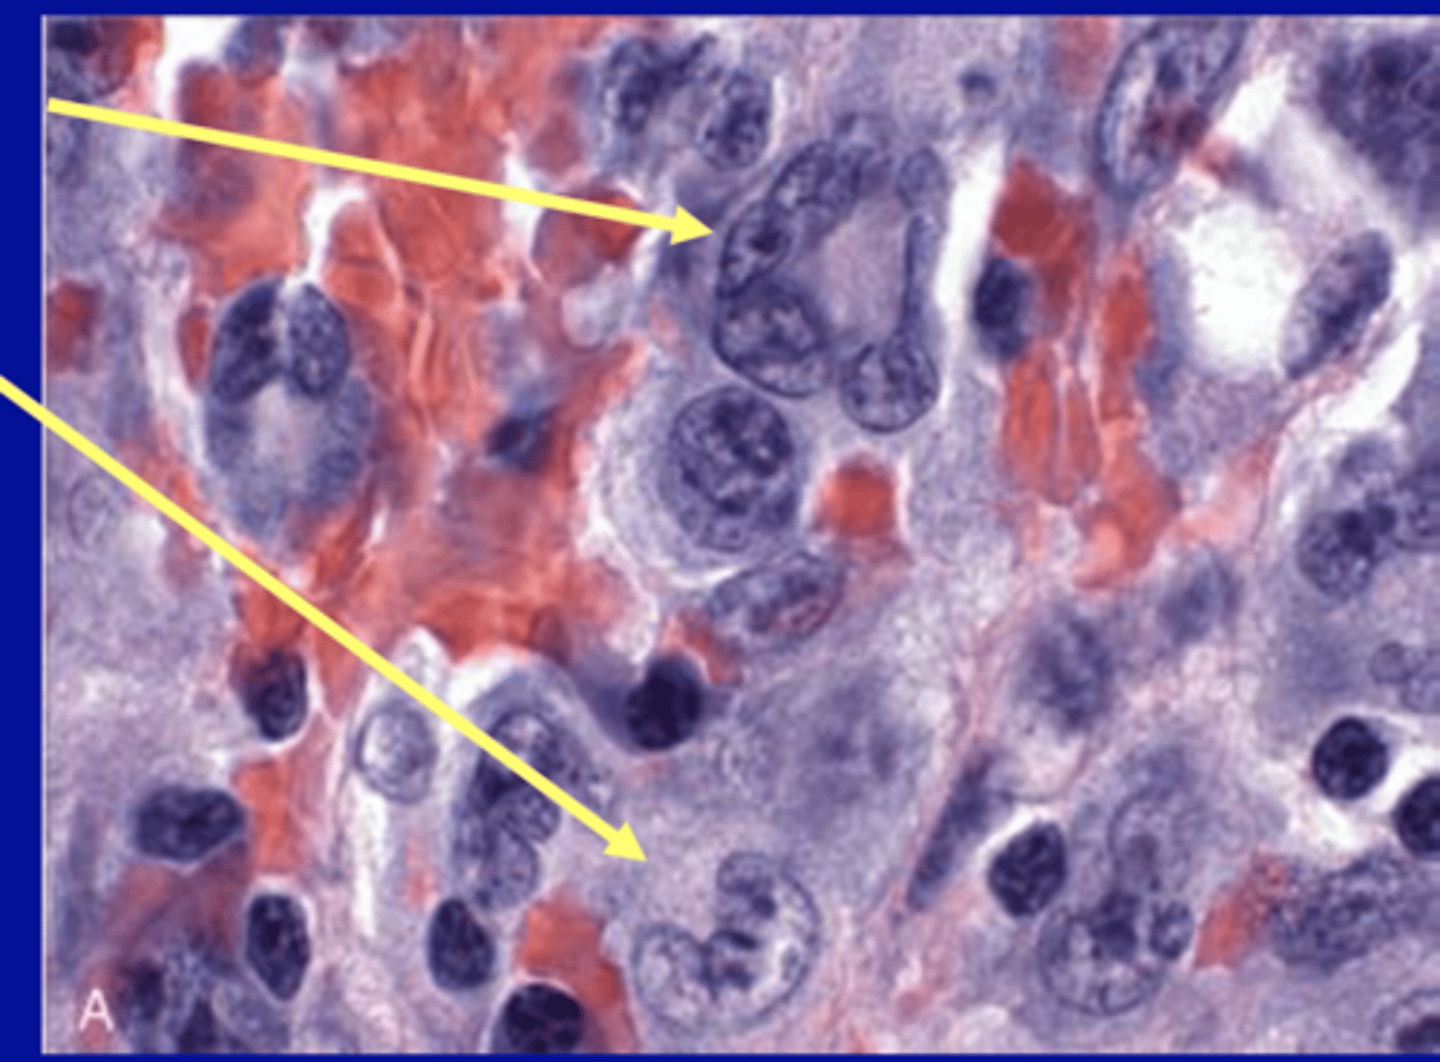

Angioimmunoblastic T-Cell Lymphoma (AITL)

-medium sized neoplastic T cells with moderate and abundant pale cytoplasm

-pronounced proliferatioin of arborizing high endothelial venules